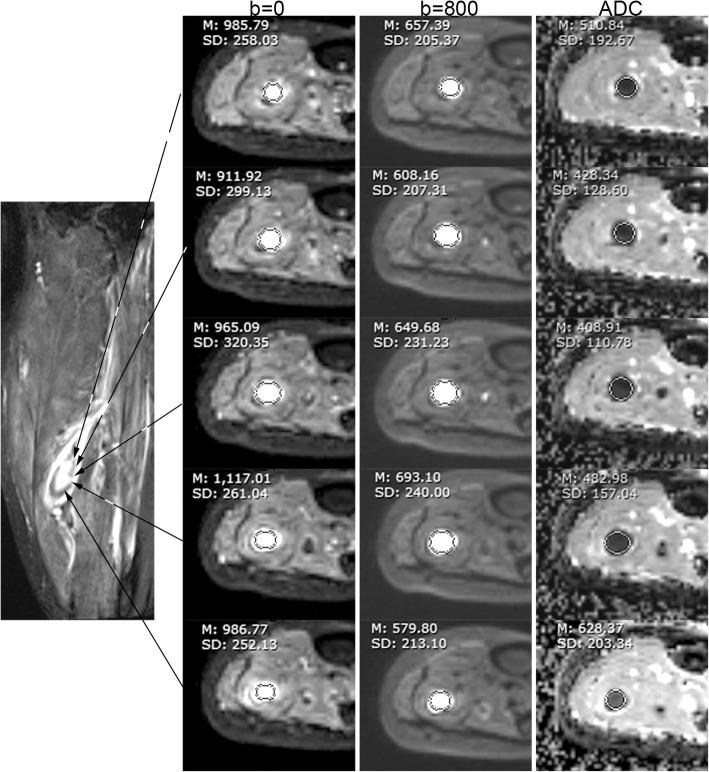

For this prospective study from December 2015 to December 2017, 85 participants (mean age = 53 years, age range = 3474) with DVT of lower extremities underwent readout-segmented DW CMR. DVT of ≤14 days were defined as acute (n = 55) and > 14 days as non-acute (n = 30). DVT visualization on b = 0, b = 800, and apparent diffusion coefficient (ADC) images were assessed using a 4-point scale (03, poor~excellent). DW CMR parameters were measured using region of interest (ROI). Relative signal intensity (rSI) and ADC were compared between acute and non-acute DVT using a Mann Whitney test. Sensitivity and specificity for ADC and rSI were calculated.

ADC maps had higher visualization scores than b = 0 and b = 800 images (2.7 ± 0.5, 2.5 ± 0.6, and 2.4 ± 0.6 respectively, P<0.05). The mean ADC was higher in acute DVT than non-acute DVT (0.56 ± 0.17 × 10 vs. 0.22 ± 0.12 × 10 mm/s, P<0.001). Using 0.32 × 10 mm/s as the cutoff, sensitivity and specificity for ADC to discriminate acute from non-acute DVT were 93 and 90% respectively. Sensitivity and specificity were 73 and 60% for rSI on b = 0, and 75 and 63% for rSI on b = 800.

本前瞻性研究于 2015 年 12 月至 2017 年 12 月纳入 85 例下肢 DVT 患者(平均年龄 53 岁,年龄 3474 岁),行分段读出 DW CMR 检查。DVT 发病时间≤14 天定义为急性(n=55),>14 天定义为非急性(n=30)。采用 4 分制(03 分,差~优)评估 b=0、b=800 及表观扩散系数(ADC)图像上的 DVT 显示情况。采用感兴趣区(ROI)测量 DW CMR 参数。采用 Mann-Whitney 检验比较急性和非急性 DVT 之间的相对信号强度(rSI)和 ADC。计算 ADC 和 rSI 的敏感性和特异性。

ADC 图的显示评分高于 b=0 和 b=800 图像(分别为 2.7±0.5、2.5±0.6 和 2.4±0.6,P<0.05)。急性 DVT 的平均 ADC 值高于非急性 DVT(0.56±0.17×10-3mm/s 比 0.22±0.12×10-3mm/s,P<0.001)。当 ADC 截断值为 0.32×10-3mm/s 时,ADC 对急性和非急性 DVT 的鉴别诊断的敏感性和特异性分别为 93%和 90%。b=0 时 rSI 的敏感性和特异性分别为 73%和 60%,b=800 时 rSI 的敏感性和特异性分别为 75%和 63%。